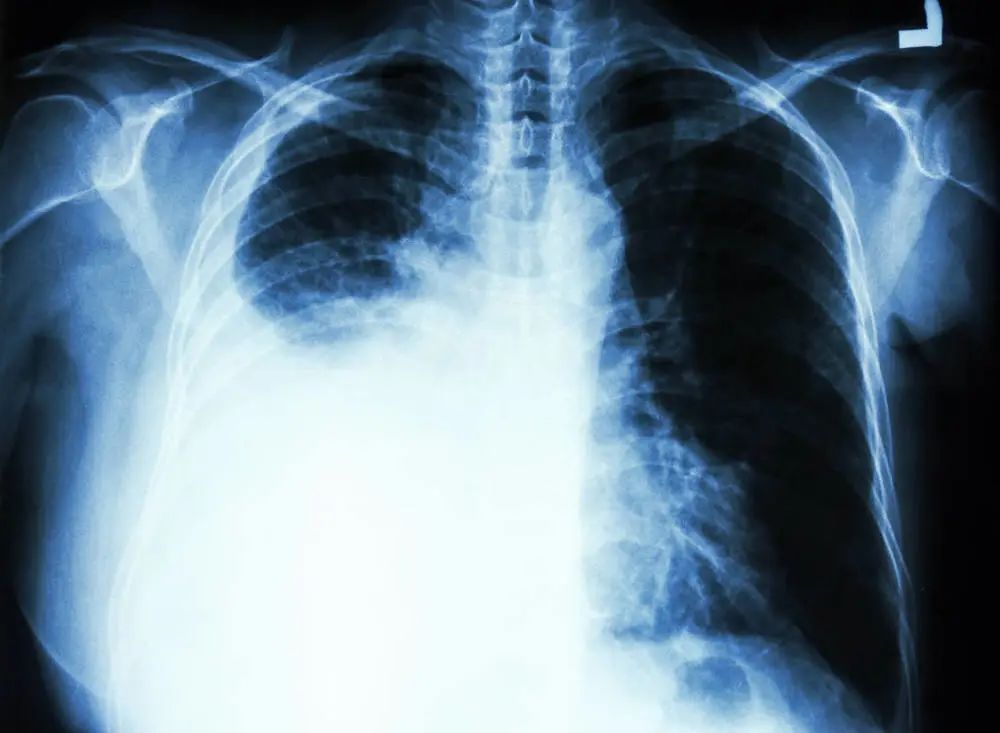

肺癌是我国发病率和死亡率最高的恶性肿瘤,并且发病率逐年上升,由于我国整理体检普及率低、防癌体检不规范,大多数患者在就诊时已达相对比较晚的分期,往往很多患者听到是肺癌晚期就十分恐慌,好像很快就要接近死亡了,但其实肺癌晚期只要积极治疗,还是可以延长生存期和改善生活质量的。

在肺癌治疗中,放疗的地位日益突出,起着重要的作用,大约有70%的肺癌患者在治疗过程中需要使用放射治疗。